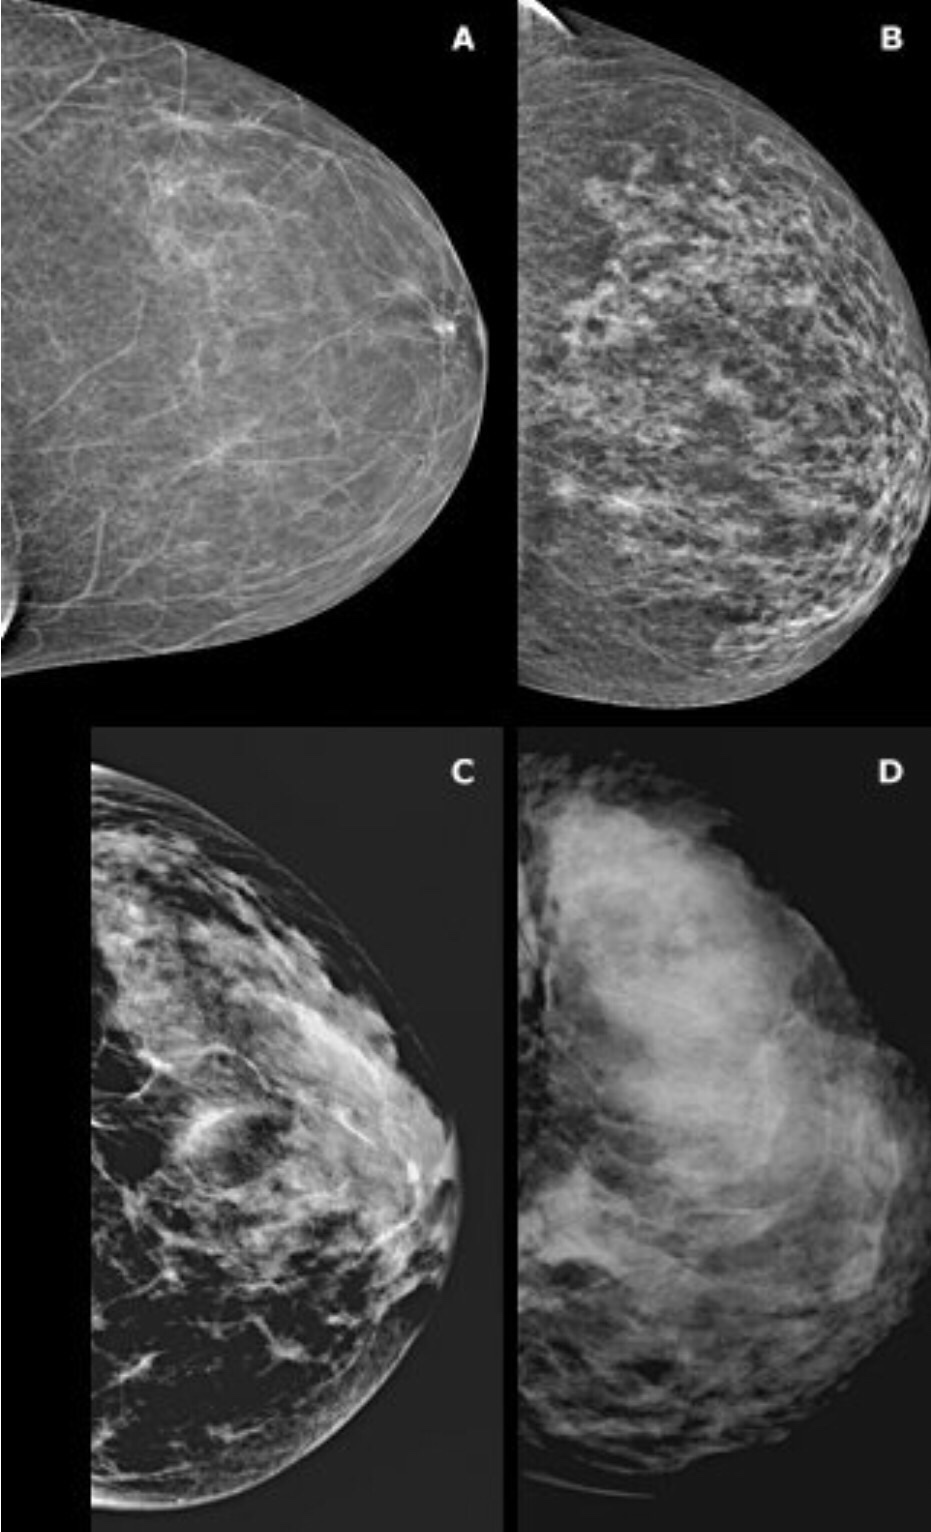

2. The Overall composition of the breast including its density. Younger women have denser breasts which reduce the sensitivity of the mammogram test in identifying sinister pathologies. The mammogram is more sensitive to pick up lesions in older women with fatty breasts (with less glandular breast tissue).

A – almost entirely fatty

B – Scattered areas of fibroglandular density

C – heterogeneously dense

D -extremely dense